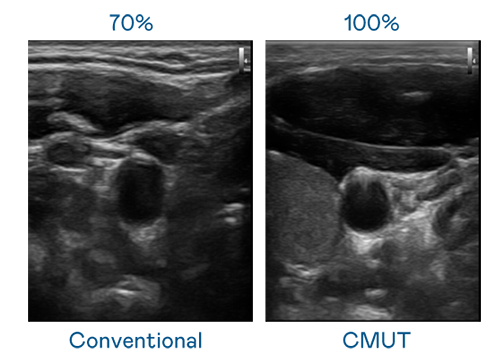

CMUT 技术是一种用电容式微机电元件来产生超音波讯号的技术。与传统 PZT 压电式技术相比,CMUT 频宽增加 30%,更宽频的超音波讯号让影像解析度大幅提升,是实现高影像品质医疗超音波扫描、促进精准医疗发展的关键技术。

超音波影像的解析度高低,首先取决于探头能发出的讯号频宽。尊龙凯龙时官网进入网页 CMUT 可提供高清晰的超音波讯号,提供高频宽、高灵敏度、影像纹理细节更高的超音波影像,协助医护人员缩短影像判读时间及利用精准的医疗影像进行诊断。